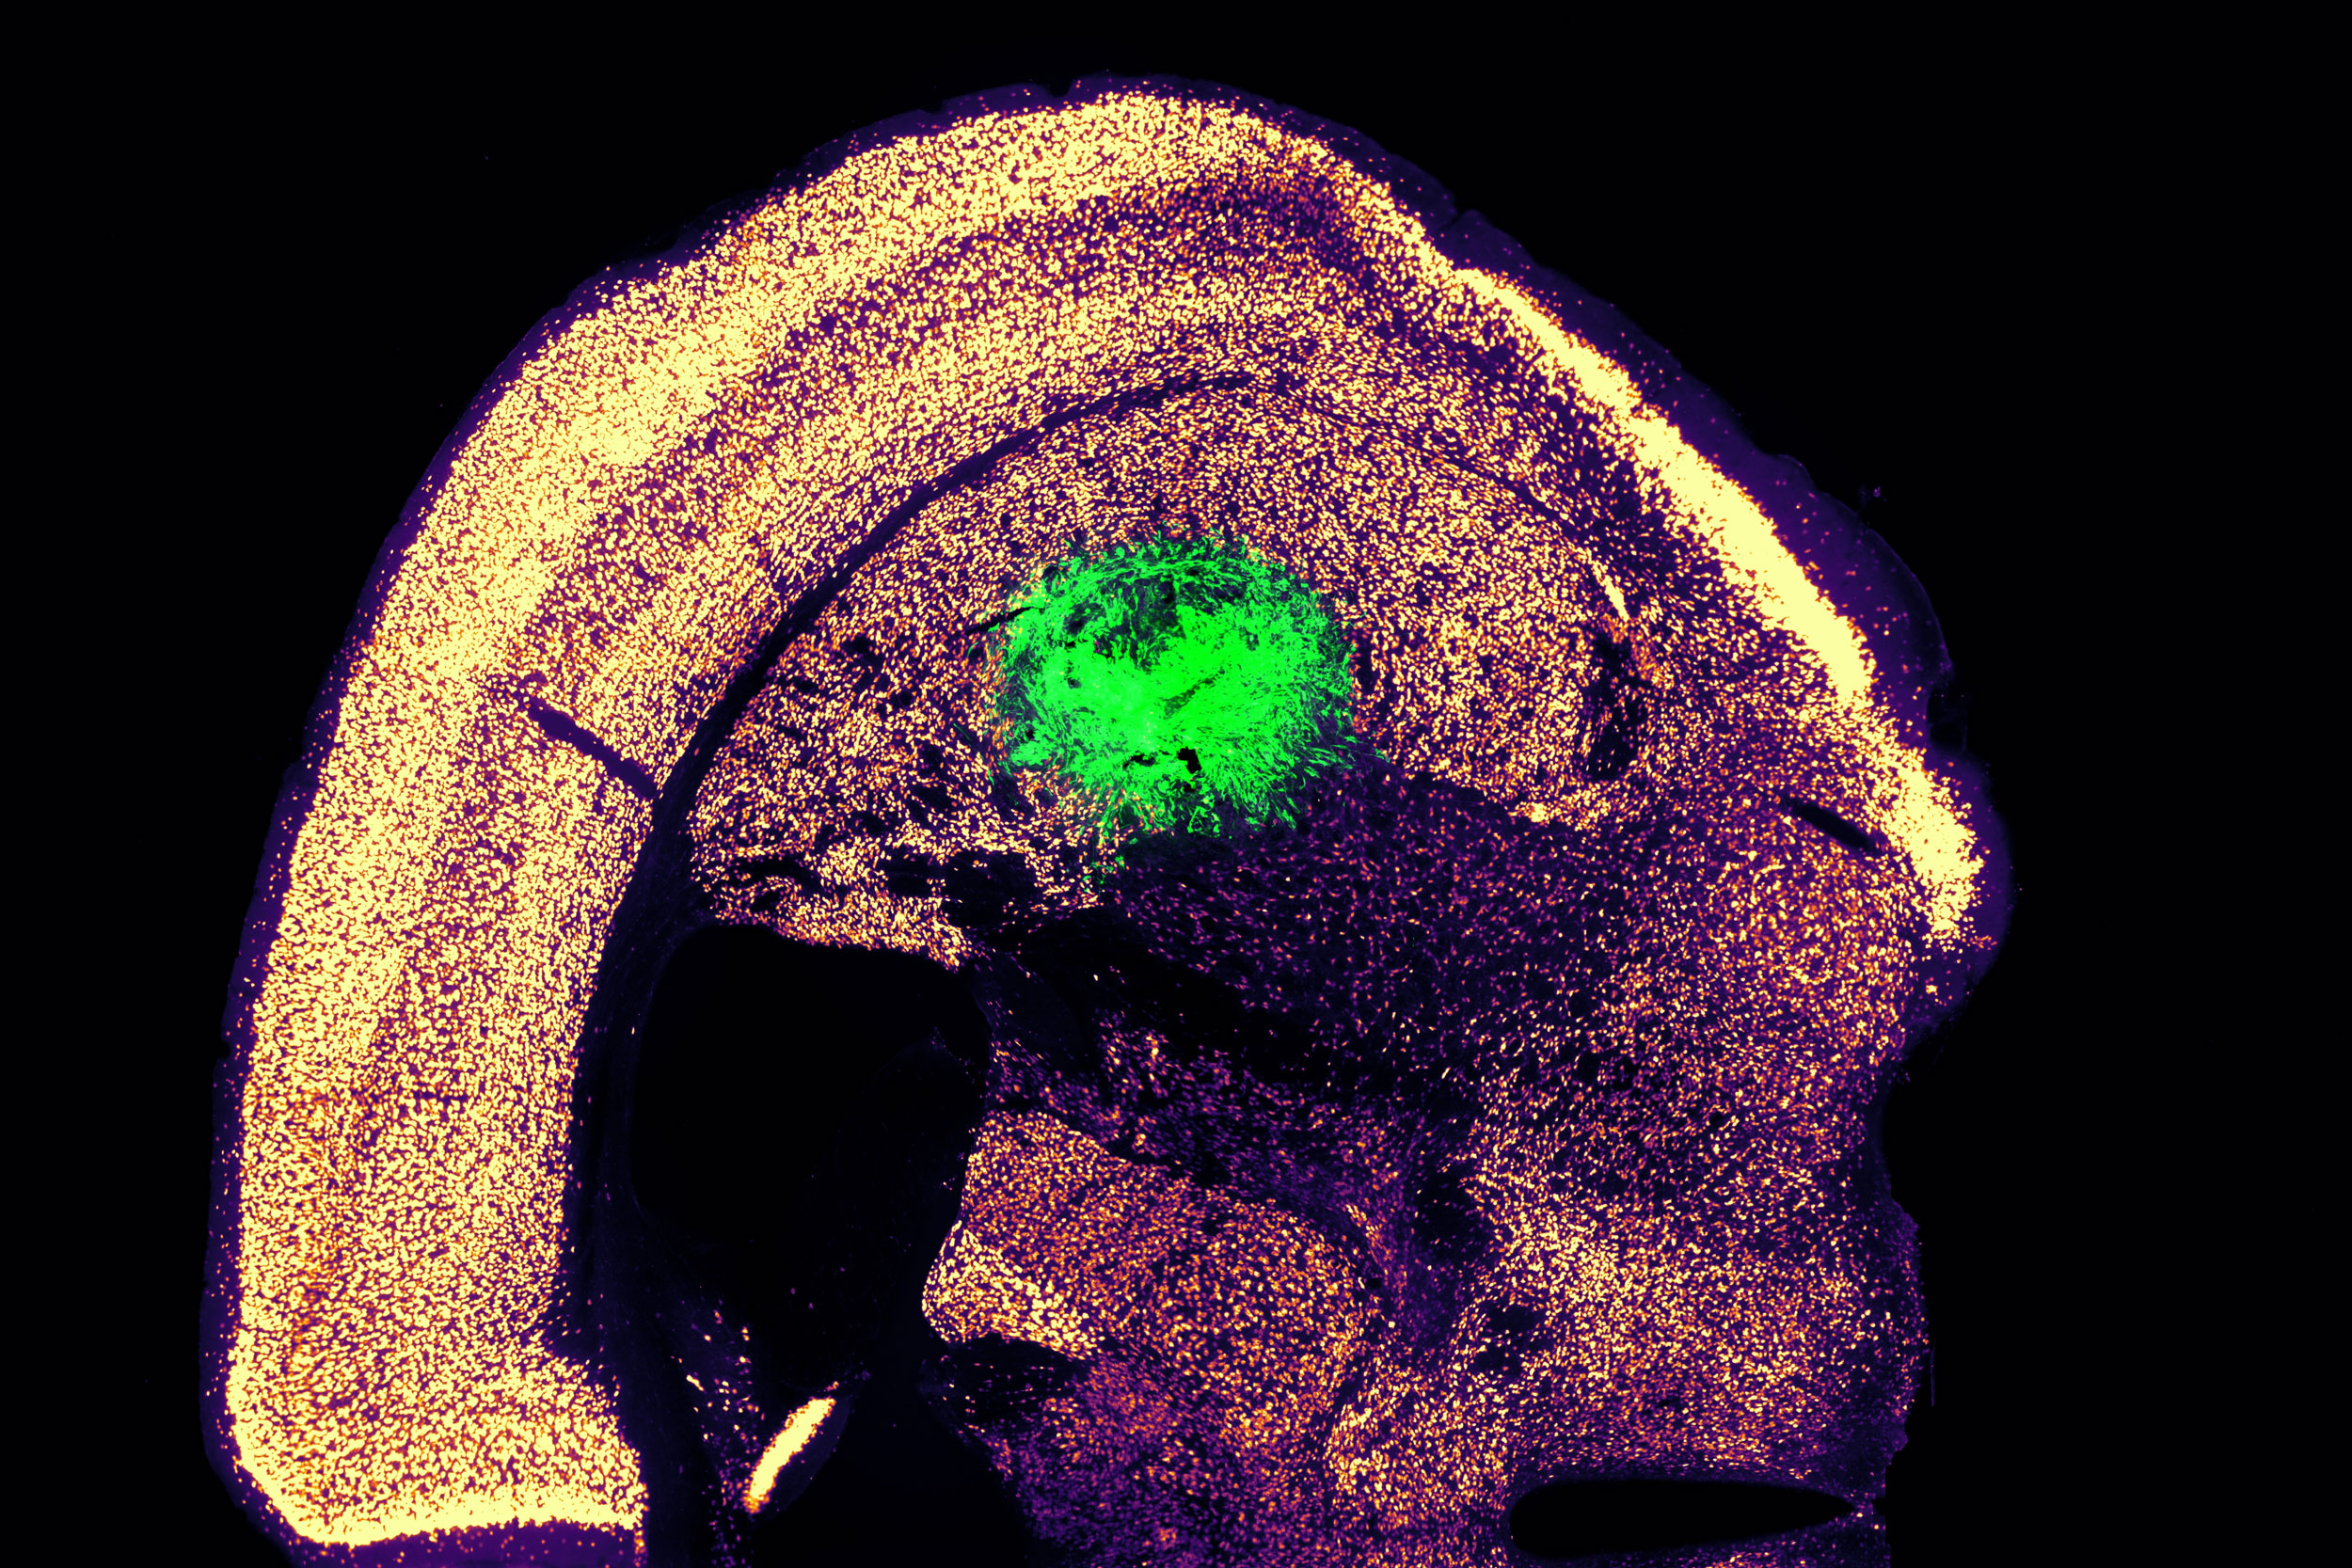

Η Katie Galloway, καθηγήτρια στο MIT, εξηγεί ότι η νέα αυτή τεχνολογία μπορεί να ανοίξει το δρόμο για θεραπείες αντικατάστασης κυττάρων. Η ομάδα της κατάφερε να δημιουργήσει κινητικούς νευρώνες και να τους ενσωματώσει στους εγκεφάλους ποντικών, όπου αλληλεπίδρασαν με τον υπάρχοντα ιστό.

Εμφύτευση κυττάρων

Αφού εντόπισαν τον βέλτιστο συνδυασμό γονιδίων, οι ερευνητές άρχισαν να εργάζονται για τις καλύτερες μεθόδους παράδοσης, που ήταν το επίκεντρο της δεύτερης μελέτης στο Cell Systems. Δοκίμασαν τρεις διαφορετικούς ιούς και βρήκαν ότι ένας ρετροϊός πέτυχε τον πιο αποδοτικό ρυθμό μετατροπής.